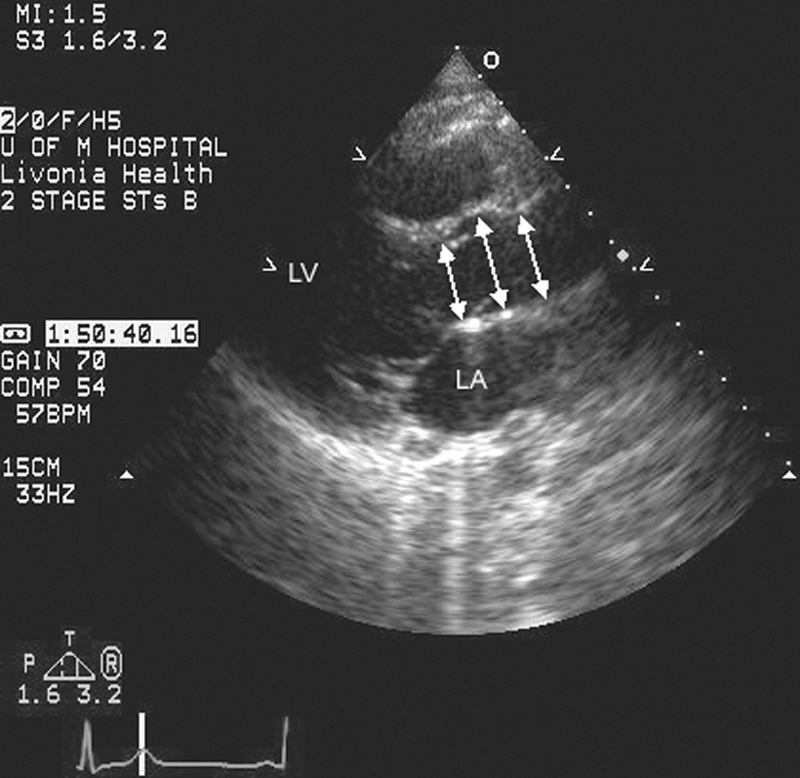

فحوصات تشخيصية لبعض امراض القلب والشرايين التاجية